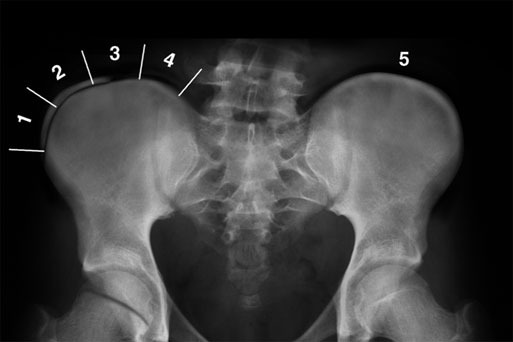

側弯の進行リスクを評価する指標としてRisser sign(リッサーサイン)があります。

これは骨盤の骨化の進行度を評価し、体の成長がどの段階にあるかを推測するものです。

骨盤の上縁(耳のような形の部分)に現れる骨化の進行を5段階で分類し、骨の成熟度を判定します。

Risser signの分類

- グレード0

骨化なし(成長期の初期で側弯進行のリスクが高い) - グレード1~3

骨化進行中(25~75%で成長が続いている) - グレード4

骨化が100%だが、骨盤との癒合は未完了(成長終盤) - グレード5

骨化と骨盤の癒合が完了(身長の伸びは終了)

骨化が進むと成長の余地が減り、側弯症の進行リスクも低下します。

そのため、Risser signとCobb角を併せて評価し、適切な経過観察や治療方針を決定します。

上記画像では3まで骨化が進んでいると判断します。

画像引用:Radiology Reference A not for profit site intended for radiologists to improve patient care